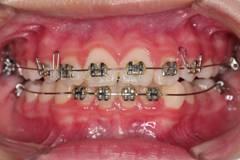

下面這個小患者就存在需早期矯正的問題。通過早期矯正,在不長的時間內(nèi)就達(dá)到極為明顯的療效。她的情況如果等到牙齒替換完畢后再解決,矯治的難度則會非常大。

早期矯正中